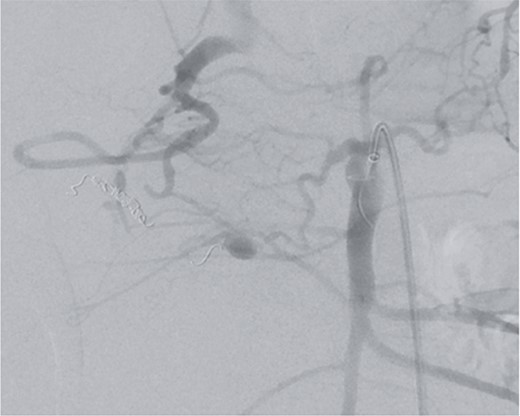

However, on the 16th day following the initial surgery, there was another active bleeding from the pancreaticoduodenal artery, distal to the previously placed coil. This bleeding was also managed interventionally (Figs 4 and 5).

Angiography showing another aneurysm with active bleeding, proximally to the previously coiled site.

Postinterventional angiography, after interventional bleeding control, using coiling.